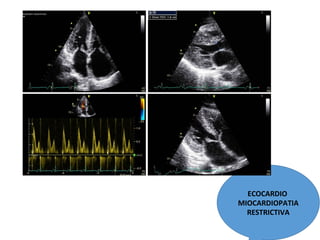

ECOCARDIO

MIOCARDIOPATIA

RESTRICTIVA